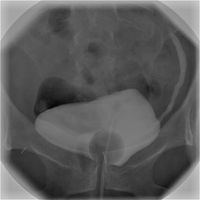

Urologie je chirurgický lékařský obor zabývající se diagnostikou a terapií chorob vylučovací soustavy a mužských pohlavních orgánů.